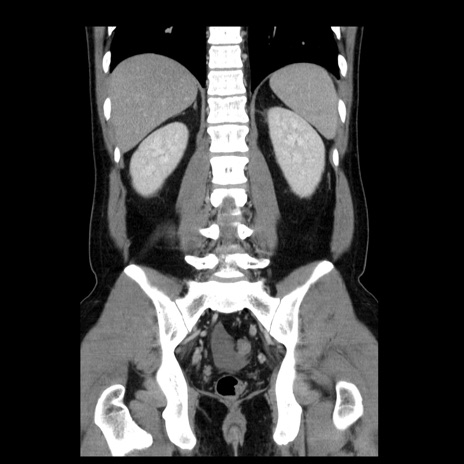

症例4(冠状断像)

【症例】30歳代男性

【主訴】腹痛、嘔吐

【現病歴】昨晩から突然の腹痛あり、その後嘔吐、軟便も出現。腹痛が改善しないため救急搬送となる。2日前にしめ鯖の食事歴あり。

【身体所見】意識清明、苦悶様、BP 135/90mmHg、BT 35.7℃、腹部:平坦、やや硬、心窩部〜臍部に自発痛、圧痛あり、筋性防御+、反跳痛-

【データ】WBC 8100、CRP 0.57